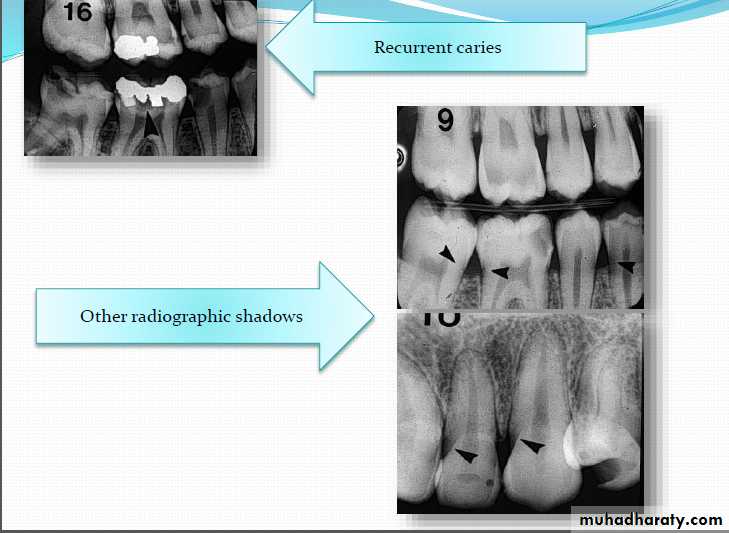

Recurrent cariesIt is diagnosed whenever there is softness due

to caries at a defective margin, and when the tip

of a periodontal probe can enter the defect

without any resistance.

A restoration with a discolored margin or a small

marginal ditch (<0.5 mm or the head of the

probe) is recorded as an early recurrent

carious area. A larger defect should be

classified as advanced recurrent carious area

There are two valid indicators of recurrent (secondary) caries:

• softness at the margin of a filling that is detectedusing an explorer or

• presence of a large defect (a minimum diameter of

0.4 mm) at a margin of a filling with softness in the

area.

Large defects are associated with a high level of colonization with cariogenic bacteria.

Marginal discoloration by itself is not a valid sign for

dental caries.

OTHER RADIOGRAPHIC SHADOWS

Radiolucent Cervical Burn out:- Evident at the neck of tooth

well demarcated above by

enamel cap& below by alveolar

bone level

- It is triangular in shape

being less apparent at the center

of tooth

-good alveolar bone height

will enhance cervical burn-out

Radiopaque zone beneath amalgam restorations

dentinTin & zinc ions are released into underlying